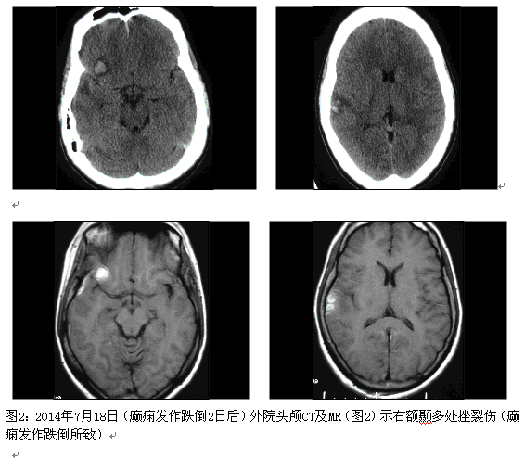

患者女性,21岁,11岁开始发作,表现:眼前出现黑色的实心圆点或黑色的正方形,双眼向右凝视带动头向右侧偏转,曾有一次伴转圈,双手握拳僵硬,严重时意识不清,仅有一次伴四肢强直阵挛,类似发作频率:从3次/月增至每日无数次,清醒、睡眠中均有发作。最长间歇期:2-3年(14岁-17岁年无发作)。曾服用土方(具体不详)。现服用奥卡西平(仁奥)300mg/早、晚;德巴金500mg/早、晚;拉莫三嗪50mg/次,每日2次;左乙拉西坦500mg/次,每日2次。2014年7月16日癫痫发作时跌倒,后头部着地,昏迷数分钟,鼻、左耳流血。

患者考虑为药物难治性癫痫,且曾有发作致脑外伤的事件,纳入术前评估。结合相关检查结果,脑电图报告:异常脑电图III(清醒/睡眠),间歇期:弥漫性,左额-中央著,发作期:临床:右侧偏转。EEG:发作型,左半球。头颅MRI薄层扫描:1.右侧颞叶皮层(含颞极)、邻近右侧额下回多发软化灶并胶质增生、含铁血黄素沉着;右侧额叶眶回局部慢性小出血灶并含铁血黄素沉着可能性大;2.待排左侧额上回与额下回交界处局灶性脑皮质发育不良;3.考虑左侧乳突炎症改变。视野检查无异常。韦氏测试:智商84,言语76,操作96,记忆<51。癫痫定位考虑为额叶外侧面,定侧为左侧,病因考虑皮层发育不良;经全中心讨论后计划一次性切除手术,切除范围,后界:中央前沟后壁,上界:额上沟外侧壁,下界:额下沟外侧壁1cm;前界:额中回后部。予术中唤醒下切除,切除过程中嘱患者讲话并交流,病变质地稍硬,将病变全部切除,约3.5*3.0*3.0cm,术后患者无语言功能障碍,随访近3个月无发作,术后病理回报:局灶性皮层发育不良FCD Ib型。